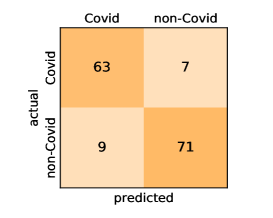

Here, we present and discuss the obtained results for detecting COVID-19 on the considered CT image datasets with different deep networks. We report the quantitative results along with the confusion matrices for every single architecture of the adopted networks.

Our models achieve fairly good performance compared with the recently published work using the exact network architectures. This can bet attributed to a better optimization of our models and the effectiveness of our fine-tuning strategy using custom-sized inputs determined specifically for each architecture. Here, we see that DenseNet201 outperforms all other architectures. The model achieves average accuracy and sensitivity scores of and , respectively. It also identifies all COVID-19 images with only four images, on the average, are falsely predicted as Non-COVID-19. DenseNet169 achieves the second best average accuracy of and a very high sensitivity identical to the best model. The DenseNet121 and Xception models have nearly identical results for all evaluation metrics. We observe that small-sized networks such as ResNet18 achieves comparable results with other deeper models. The SqueezeNet and ShuffleNet models perform at a similar level of accuracy. The variants of the ResNeXt models have comparable results and perform as good as the different ResNet variants. A detailed analysis on the class-wise results for individual models is presented in the confusion matrices in Figure 10.